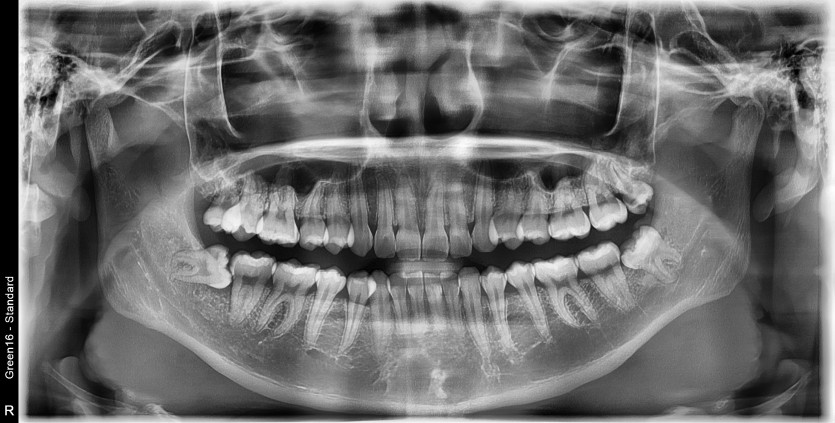

#18,28,38,48 사랑니 발치

구강 외과 전문의가 당일 발치했습니다.